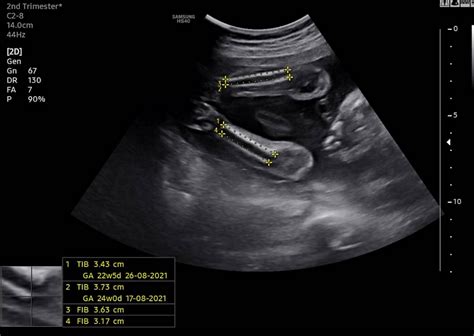

Jan 20, 2024 · Understanding Ultrasound Scans: From 2D to 5D 🤰🖤 Ultrasound technology has advanced remarkably, offering various scan types to monitor your baby's growth and health during pregnancy. Let's dive into what 2D, 3D, 4D, and 5D ultrasounds mean and how each provides unique views of your little one! 🌟 **2D Ultrasound** The classic 2D ultrasound uses sound waves going into the body and.

Nov 3, 2022 · Untuk merakam gambar muka dan jantina baby untuk dijadikan kenangan. • Scan 4D 5D juga sesuai untuk lihat bahagian bibir baby dengan lebih jelas. • Scan 4D lebih kepada merakam video manakala 3D merakam imej. . . Semua ibu yang hamil, digalakkan untuk lakukan scan 2D secara berkala untuk memastikan bayi sentiasa sihat. Jangan lupa.